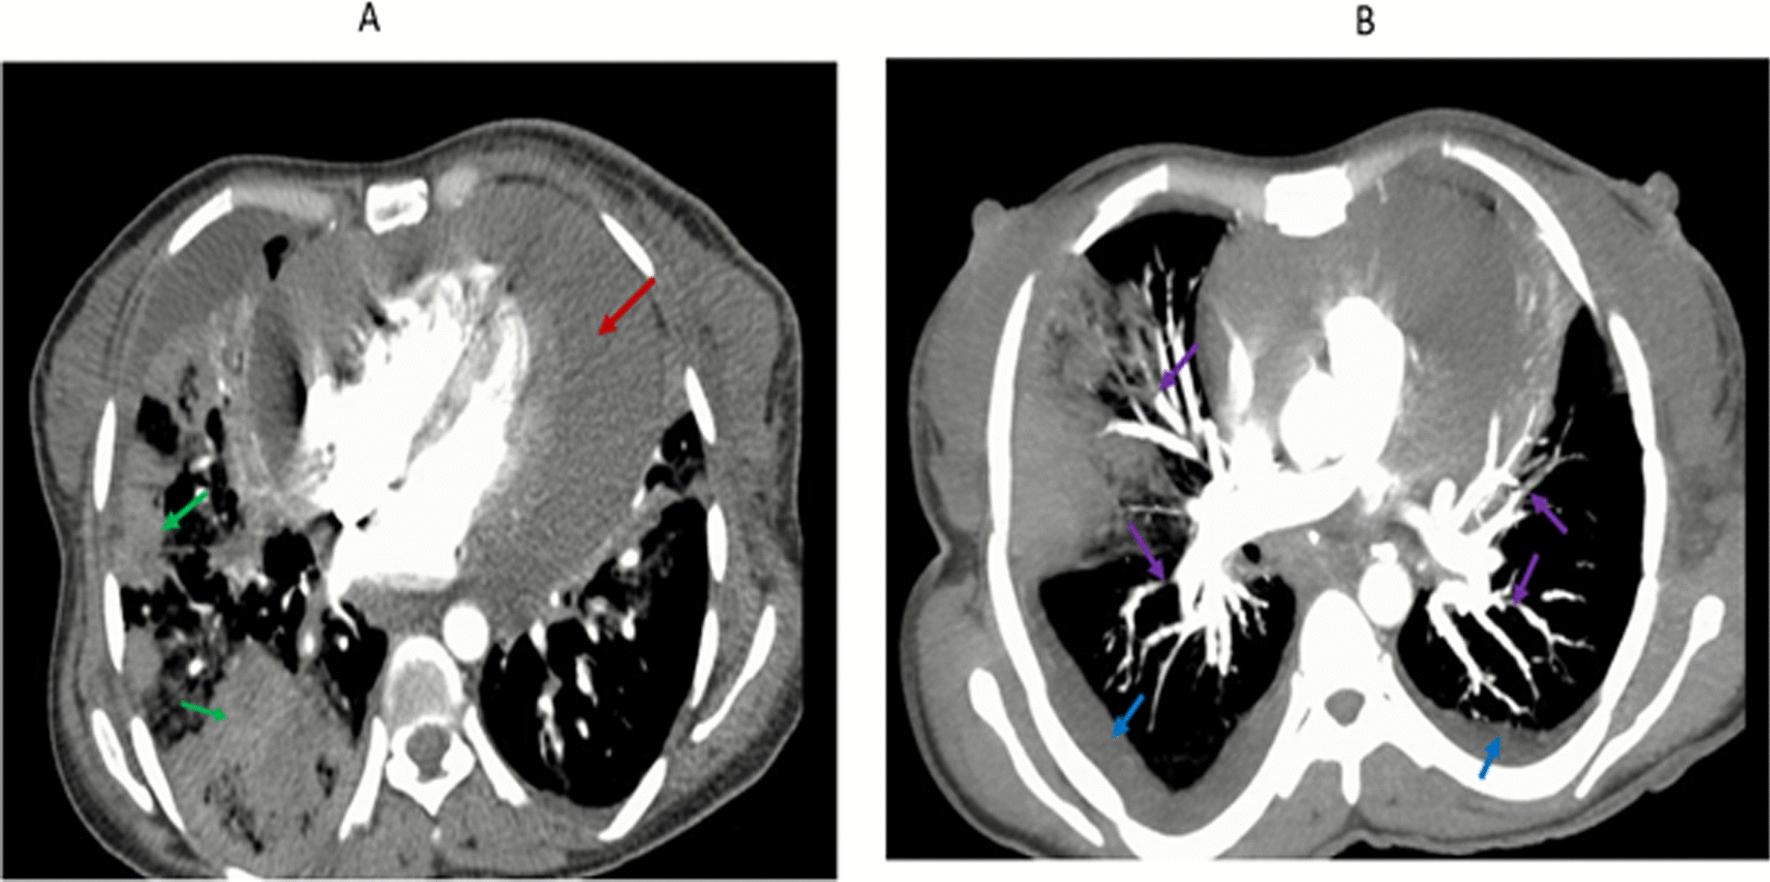

A 35-year-old Black woman presented with shortness of breath at rest, orthopnea, paroxysmal nocturnal dyspnea, chest pain, a blood-tinged productive cough, and fever for 2 weeks. She also had progressive body swelling, easy fatigability, loss of appetite, and abdominal pain during the same week's duration. Body imaging revealed large pleural and pericardial effusions, metastatic liver lesions, and bilateral pulmonary vascular segmental and subsegmental filling defects. Pericardial and pleural fluid cytology suggest malignant effusion. Liver lesions and core needle biopsy indicated adenocarcinoma of unknown origin, and the carcinoembryonic antigen level also increased significantly.

一名 35 岁的黑人女性因静息时呼吸困难、端坐呼吸、阵发性夜间呼吸困难、胸痛、血性痰和发热 2 周而就诊。在同一周内,她还出现了进行性身体肿胀、易疲劳、食欲不振和腹痛。身体影像学显示大量胸腔和心包积液、转移性肝病变以及双侧肺血管节段和亚节段充盈缺损。心包和胸腔积液细胞学检查提示恶性积液。肝病变和芯针活检提示腺癌,癌胚抗原水平也显著升高。